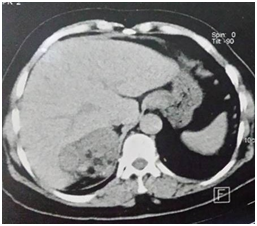

A CT scan showed a right lesional adrenal process, well confined by lobulated contours, hypodense, containing greasy spots and calcifications (Figure 1), heterogeneously enhanced after a contrastive injection (Figure 2), measuring 71×60×55mm.

Figure 1 Abdominal CT scan showing the right adrenal mass hypodense containing greasy spots.